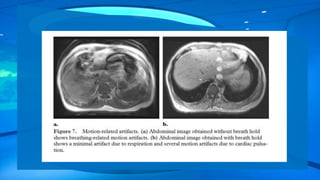

The best way to eliminate respiration-related motion is to perform breath hold. However, the

number of sections that can be obtained during a 20-second breath hold is limited.

Motion-related Artifacts The artifactappears as blurring of the image as well as ghosting in the phase encoding direction. The time difference in the acquisition of adjacent points in the frequency encoding direction is relatively short (order of microseconds) and is dependent on the sampling frequency or the bandwidth used. The time difference in the acquisition of adjacent points in the phase encoding direction is much longer and is equal to the repetition time used for the sequence . Respiratory and cardiac motion also can cause movement-related artifacts in the phase encoding direction.

The best wayto eliminate respiration-related motion is to perform breath hold. However, the number of sections that can be obtained during a 20-second breath hold is limited.